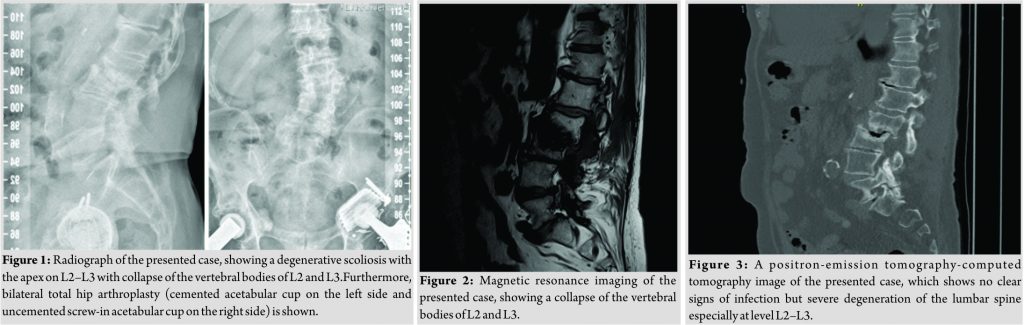

A 78-year-old male patient was referred to our tertiary, university hospital outpatient clinic with pain in his right leg. His medical history included a laminectomy of L3-L5, performed 1.5 years before his current visit, because of spinal stenosis as a result of degenerative scoliosis. This procedure was followed by the collapse of the vertebral bodies of L2 and L3 with compression of the right nerve root and spinal stenosis at L3. There had not been any wound problems or other complications after the first procedure. Further medical history included bilateral total hip arthroplasty, revision of the left hip arthroplasty after 19 years, left total knee arthroplasty, hypertension, and ulcerative colitis (without medication). The physical examination showed a lumbar scoliosis with a painful and slightly reduced range of motion of the spine whereas the sacroiliac and hip joints showed a pain-free and normal range of motions. The knee and Achilles tendon reflexes were lower on the right side. Sensation and motor function were normal. The radiographs (Fig. 1) and magnetic resonance imaging (MRI)(Fig. 2) showed degenerative scoliosis with the apex on L2-L3 with the collapse of the vertebral bodies of L2 and L3. Serum markers for infection, 2 months before the presentation at our clinic, were as follows: C-reactive protein (CRP) <1 mg/L, leukocytes 8.8 × 10 e9/L, and erythrocyte sedimentation rate (ESR) 12 mm/h. To exclude a possible spondylodiscitis, as a cause of the sudden vertebral body collapse a positron-emission tomography-computed tomography scan was performed, which showed no clear signs of infection but severe degeneration at level L2-L3 (Fig. 3). We planned a surgical decompression of L2-L3 on the right side with a posterior spondylodesis of L1-L5. During the ambulatory waiting time before surgery, the patient’s symptoms worsened. He was unable to walk and stand because of severe pain in the lumbar spine, without signs of neurological impairment. Four weeks before the onset of progressive symptoms, a broken molar was removed during a dental procedure. The patient interview revealed no alternative explanation for his worsening condition. He was admitted to the hospital, and the date of surgery was advanced. Serum infection markers showed a CRP of 174 mg/L, leukocytes of 11.9x10e9/L, and ESR of 128 mm/h. A new MRI scan showed the previously seen destruction of L2-L3, with an extensive fluid collection in the remaining intervertebral space, paravertebral myositis, and multiple abscesses (Fig. 4). Based on the new clinical situation, a decompression of L2 and L3 and a posterior spondylodesis T12-L5 was performed obtaining deep cultures of tissue and the abscess in the disc space. Vancomycin and ciprofloxacin were started postoperatively. Weakness of the right quadriceps was observed in the first postoperative hours, and a CT-scan (Fig. 5) showed a medial position of both L4 screws. These were replaced by using a revision procedure in the same day. Unfortunately, the weakness persisted in the following weeks. All intraoperative cultures showed P. micra, and the antibiotic treatment was changed to penicillin intravenously (12 g daily) based on the sensitivity spectrum. The pain and infectious signs subsided, and the serum infection markers improved after 2 weeks of antibiotics as follows: CRP 43 mg/L and leukocytes 9.3 × 10 e9/L. The antibiotic treatment was continued orally with clindamycin (600 mg three times daily) for 4weeks. At the last visit to the outpatient clinic, at 1year after surgery, the patient reported only occasional back pain. Blood results as follows: CRP 8 mg/L, leukocytes 8.6 × 10e9/L, and ESR 32 mm/h. Radiography of the spine (Fig. 6) showed unchanged spinal instrumentation and no signs of spondylodiscitis relapse.